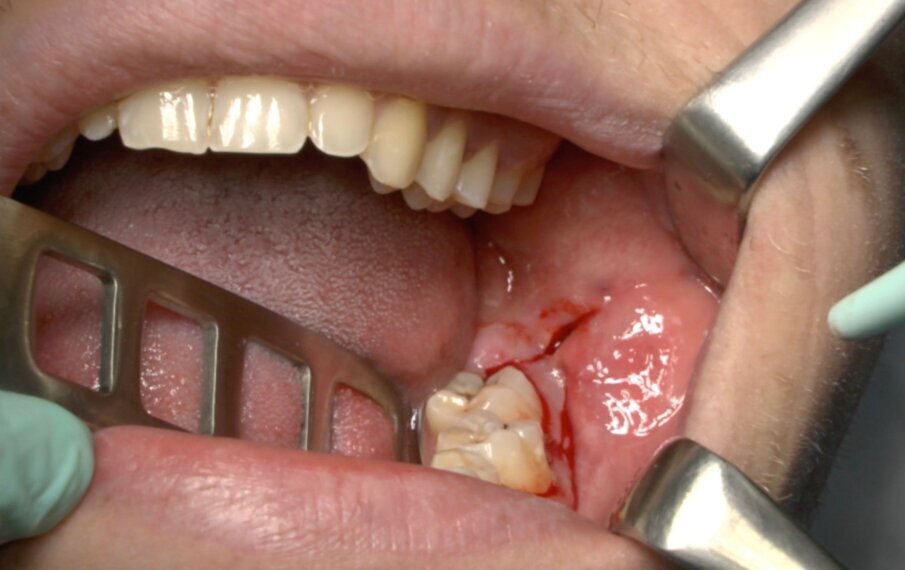

Protocollo standard

Ai pazienti viene prescritta una profilassi antibiotca con 2 gr di amoxicillina 1 h prima dell’intervento, si esegue quindi un anestesia di tipo tronculare con lidocaina senza vasocostrittore, poi infiltrazione di tipo plessica con adrenalina in corrispondenza del nervo buccinatore. Si scolpisce quindi un lembo a tutto spessore di tipo triangolare con incisione orizzontale alla base delle papille tra sesto e settimo ed incisione di scarico distale con andamento vestibolare (Figg. 1-4). Si procede con l’osteotomia che può essere eseguita con strumenti rotanti montati su manipolo retto oppure con terminale piezoelettrico con gli inserti dedicati. Qualora sia necessario si effettua l’odontotomia e la separazione radicolare con frese al carburo di tungsteno montate su turbina, quindi si esegue la lussazione e l’avulsione dell’elemento dentario. Si procede alla revisione della cavità alveolare con abbondante lavaggio con soluzione fisiologica, riempimento con collagene e sutura a punti staccati in seta 4/0. Il paziente viene dimesso con terapia analgesica ed antibiotica di supporto (Figg. 5-15).

Fig. 9_Frattura della corona sezionata mediante leva dritta.

Fig. 10_Cavità alveolare residua.